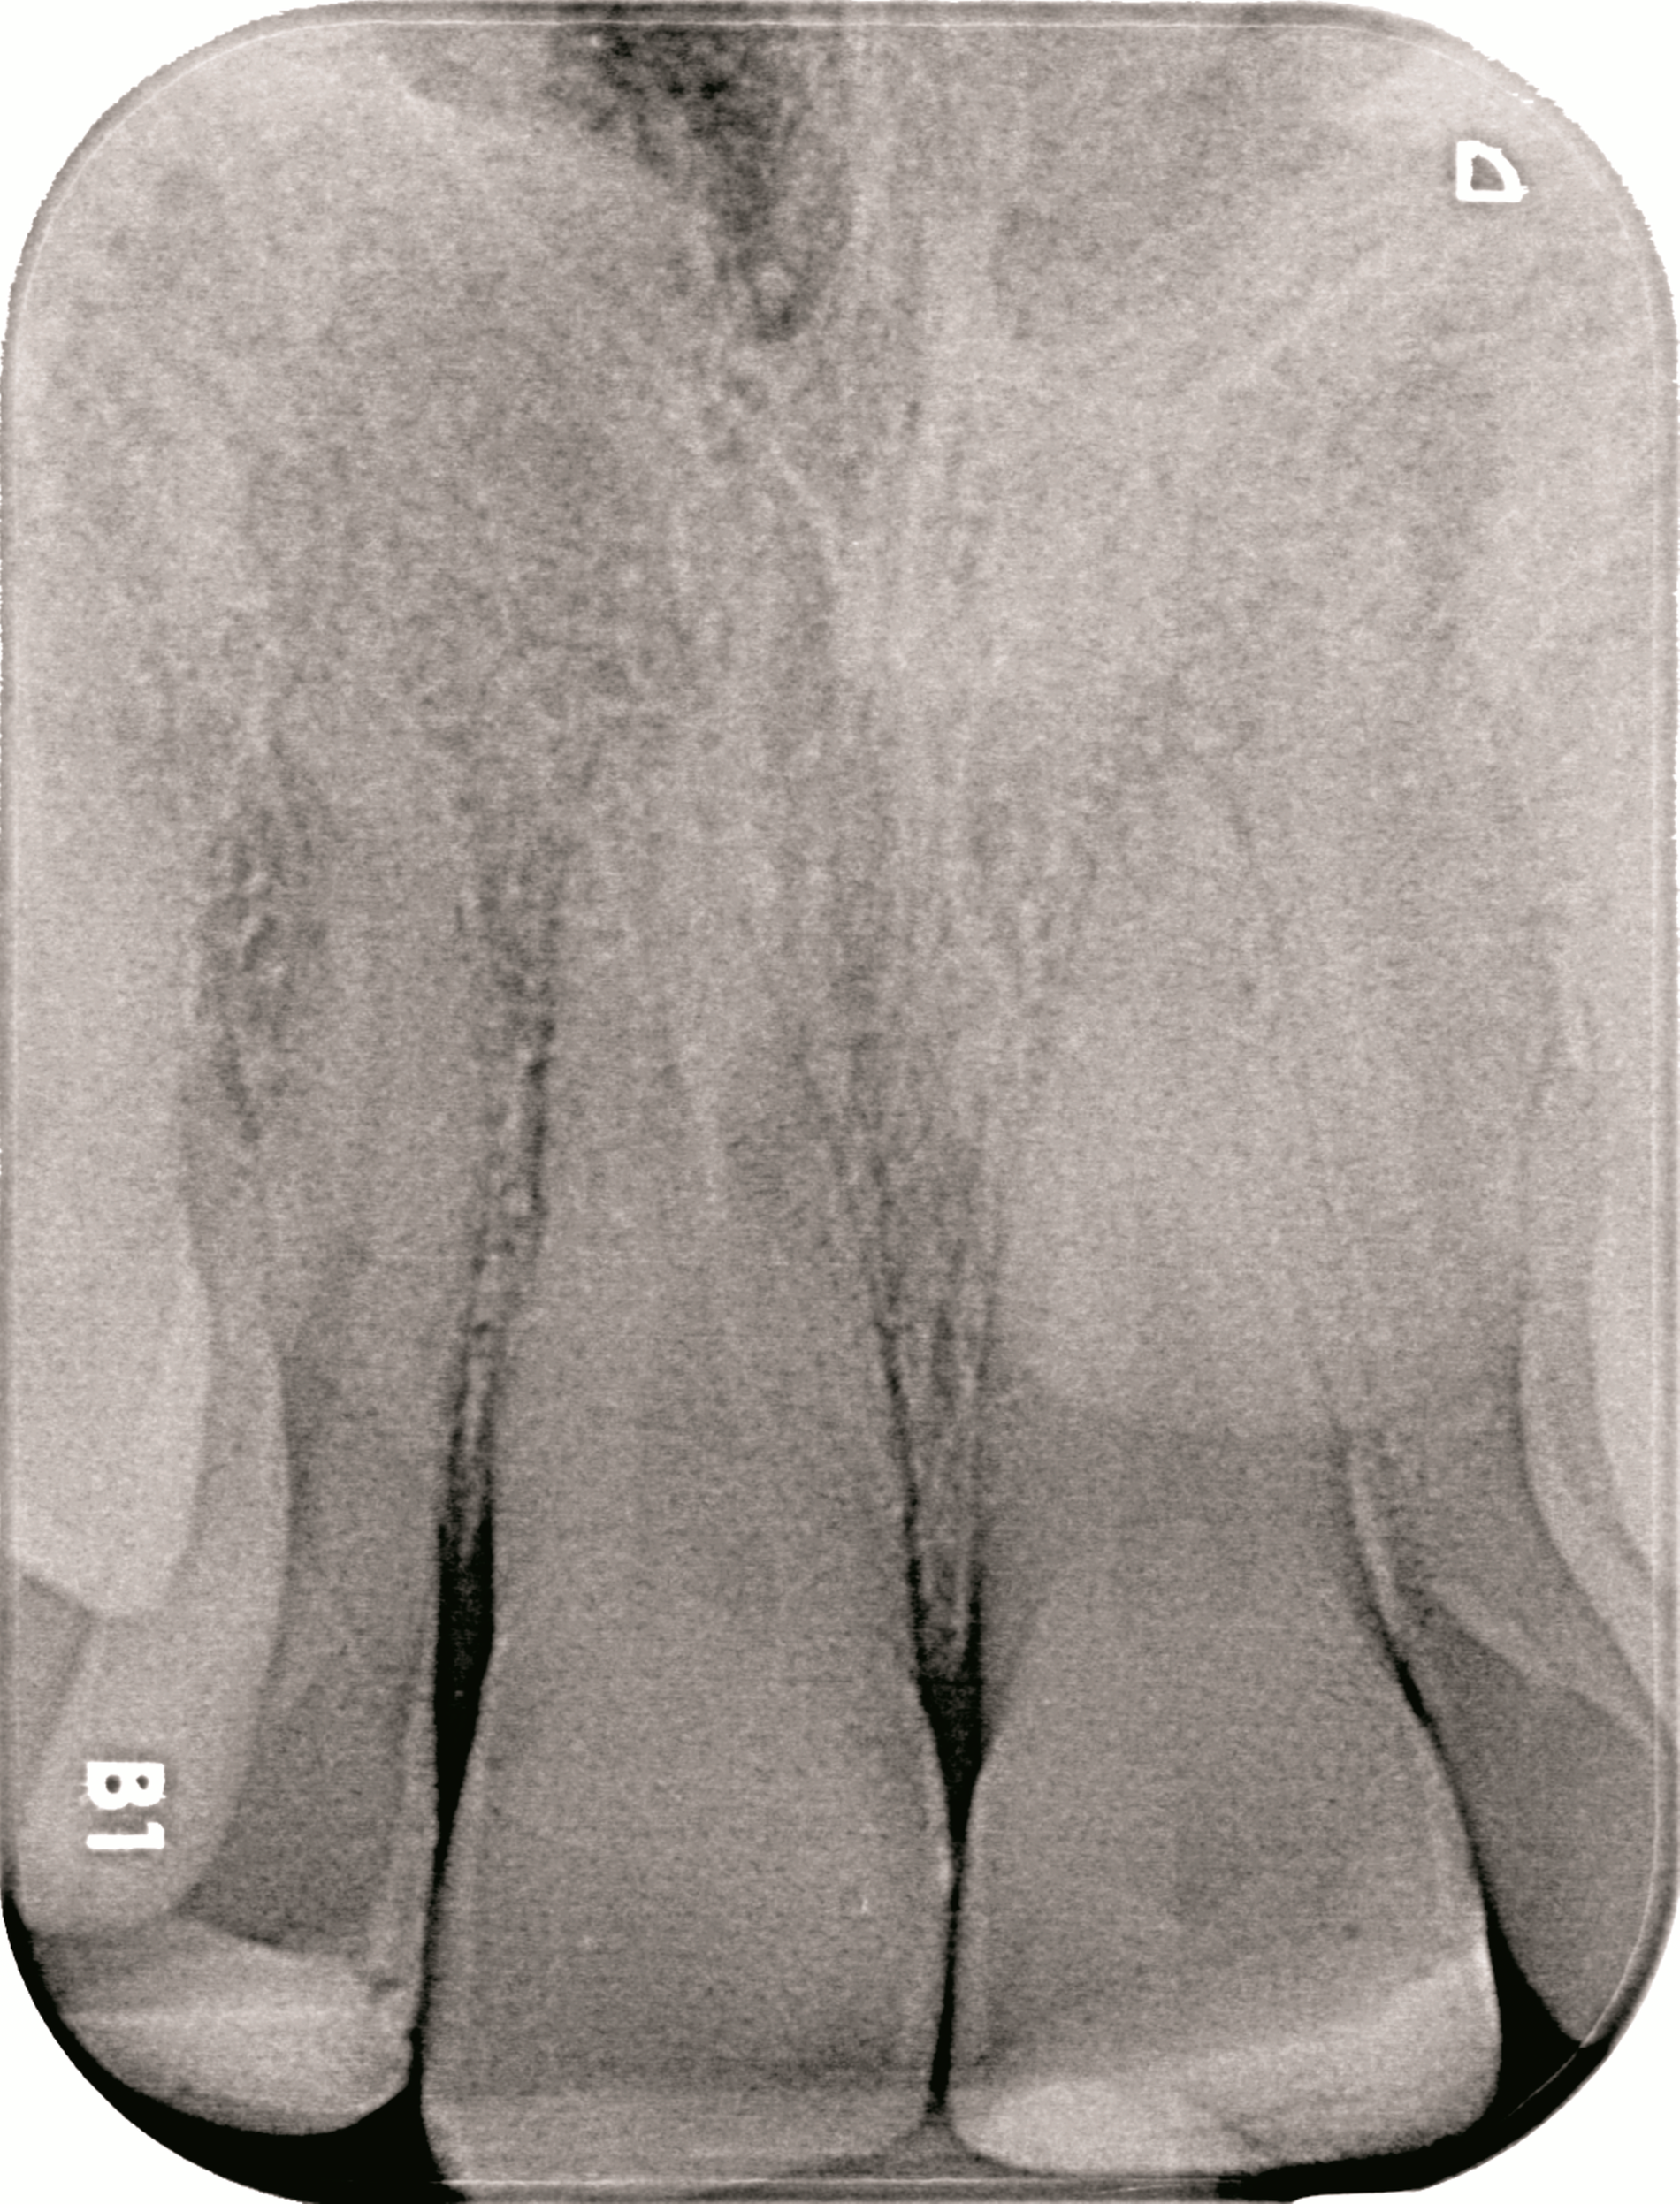

Zur Vorbereitung ist eine Rehydrierung des etwa drei Stunden trocken gelagerten Fragments, beispielsweise im Drucktopf für 60 Minuten, notwendig. Dadurch werden bestmögliche Voraussetzungen für den adhäsiven Verbund sowie eine ideale Farbanpassung geschaffen. Vor der Wiederbefestigung des Fragments werden außerdem der Sulkus des Zahnes 11 auf verbliebene Teilfragmente und der Zahn auf mögliche Wurzellängsfrakturen untersucht (Zahnfilm-Abbildung 1e). Nach Infiltrationsanästhesie wird der subgingivale Defekt mithilfe einer Gingivektomie und anschließender Blutstillung vorsichtig dargestellt, wodurch eine ausreichende Trockenlegung für das adhäsive Reattachment erzielt werden kann. Das Fragment wird anschließend mit Aluminiumoxid (50 µm) abgestrahlt, die Frakturfläche an Zahn 11 sowie das Fragment werden mit Phosphorsäure konditioniert.

Die adhäsive Konditionierung erfolgt durch ein Ein-Schritt-Adhäsivsystem, das nach dem Auftragen nicht polymerisiert wird, um die exakte Passung des Fragments nicht zu beeinträchtigen. Anschließend wird die Frakturfläche dünn mit einem dualhärtenden Befestigungskomposit bestrichen, anschließend das Fragment repositioniert. Nach vorsichtiger Entfernung der Überschüsse, insbesondere im Sulkus, wird lichtpolymerisiert, abschließend die Okklusion überprüft und der Zahn 11 poliert (Abbildung 2).